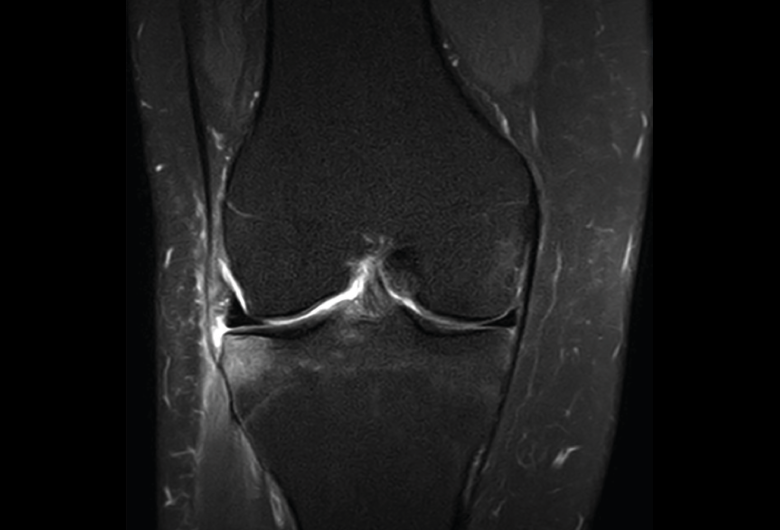

Figura 32. Corte de secuencia coronal T2 Fat-Sat de resonancia magnética de rodilla: rotura de menisco interno horizontal.